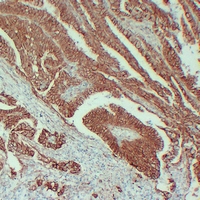

IHC (Immunohistochemistry)

(Immunohistochemical analysis of Beta-catenin staining in human colon carcinoma formalin fixed paraffin embedded tissue section. The section was pre-treated using heat mediated antigen retrieval with sodium citrate buffer (pH 6.0). The section was then incubated with the antibody at room temperature and detected using an HRP conjugated compact polymer system. DAB was used as the chromogen. The section was then counterstained with haematoxylin and mounted with DPX.)